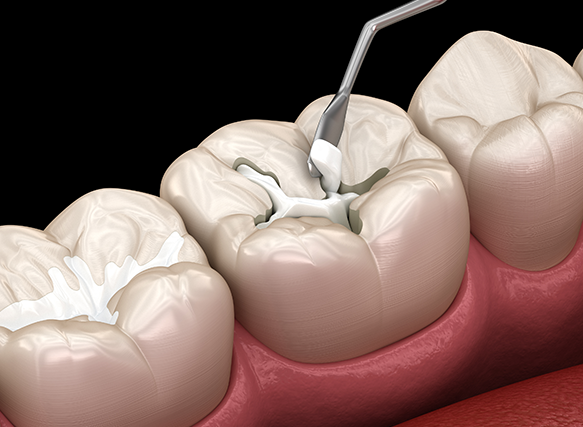

세라믹 인레이 (e.max)

자연치아와 유사한 색감·투명도, 심미성과 강도 우수

골드 인레이

인체 친화적, 마모 적고 변형 거의 없음, 강한 교합에도 적합